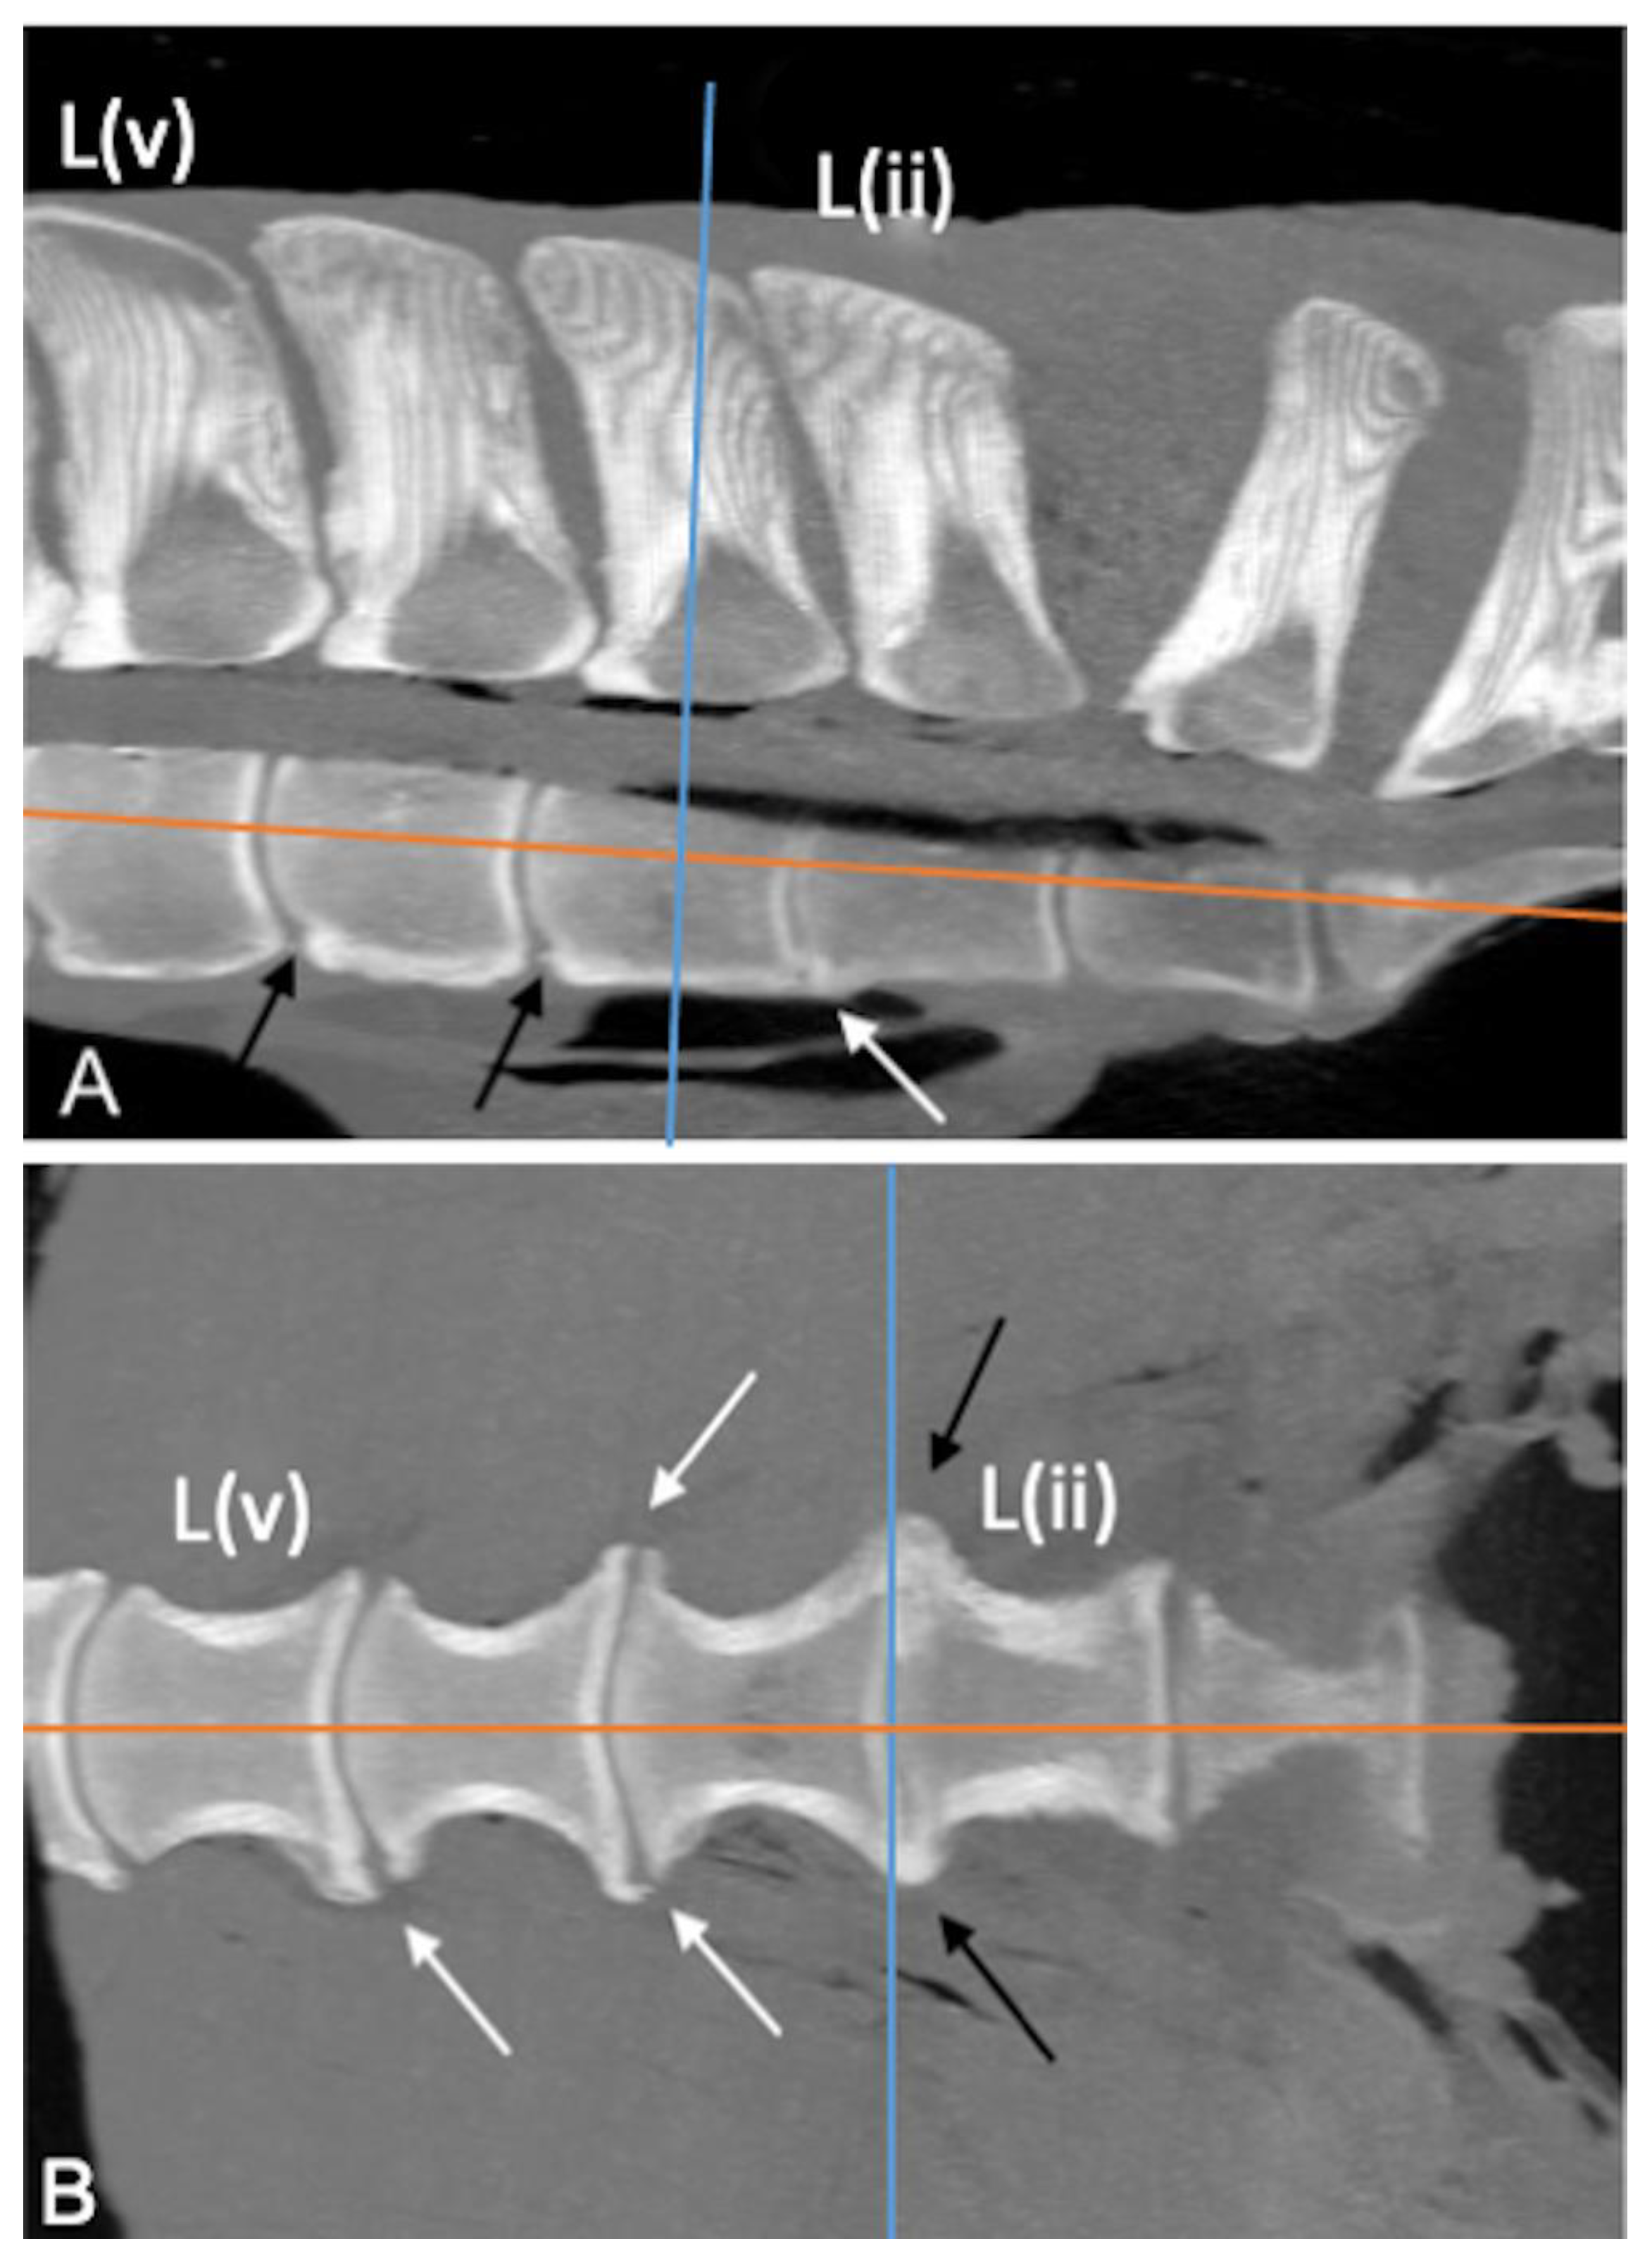

The CT appearance of two specimens without abnormalities [6] was characterized by homogeneous bone density (HU) of the bony structures (SPs, APJs, ITJs, and vertebral bodies). Differences in bone density between cortical (>1000 HU) and trabecular bone (>300 HU) of the vertebral structures were observed [19]. The periarticular bone margins were regular, and well-defined joint spaces were detected (Figure 1).

Figure 1. Sagittal ((A); cranial is toward the left), dorsal ((B); cranial is toward the top) and transverse ((C); dorsal is toward the top) multiplanar reconstruction computed tomographic images of the lumbar specimen 5, using maximum intensity projection. (A) Presence of visible intervertebral space and absence of spondylosis, spondylolisthesis and lumbar spinous processes contact or fusion. Note the spinous process (SP) of L(i) perpendicular to the orientation of the column axis, mild irregularity of the bone surface of the L(ii) SP onto the dorsocranial aspect and contact between the S1 and S2 SPs and moderate irregularity of the dorsocaudal aspect of the S1 SP and dorsocranial aspect of the S2 SP; fusion of the ventral portion and part of the middle portion of the S1-S2 SPs (B,C) Regularity of the articular margins and the joint space of the L(ii)-L(i) intertransverse joint and L(ii)-L(i) articular processes joint (arrow); the L(ii)-L(i) intertransverse space is mildly narrowed on the abaxial aspect. L(i): the most caudal lumbar vertebra.